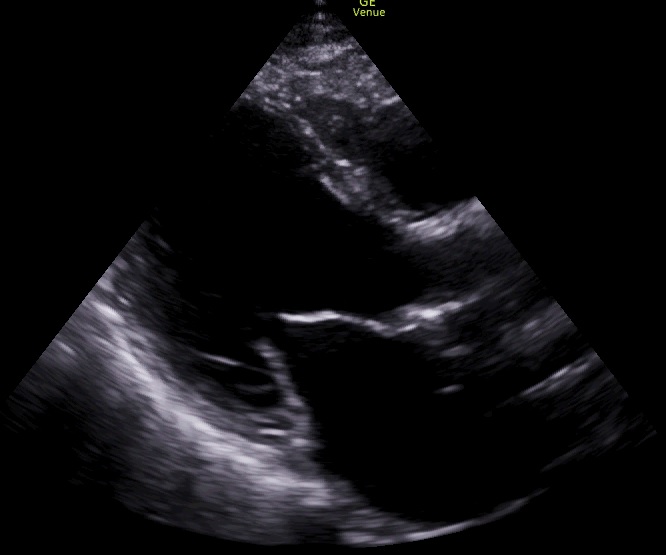

Se realiza ecoscopia a pie de cama en la que se visualiza una fracción de eyección del ventrículo izquierdo (FEVI) disminuida. Se compara con ecocardiograma reglado anterior en el que la FEVI estaba conservada.

A su llegada a urgencias, solicitan analítica que confirma insuficiencia cardíaca con valores de NTproBNP elevados (> 2500). Además personal de urgencias repite la ecoscopia confirmando FEVI reducida.

Tras el alta, vuelve a consulta para seguimiento, con buena evolución de edemas en miembros inferiores, mejoría clínica significativa. Se realiza nueva ecoscopia, en la que persiste FEVI deprimida, pero con mejoría sintomática.